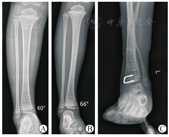

早在上世纪40年代,Phemister[22]首次提出了通过骺板阻滞的方式治疗儿童骨骼畸形的理念。随后,Stevens等[9,23]在这个基础上进一步提出了引导性生长的概念,结合工程力学通过内固定抑制一侧骺板生长,保留对侧骺板正常生长,从而实现矫正骨骼成角畸形。胫骨远端用于骨骺阻滞常用的张力螺钉有"8"字板螺钉和Blonut订书钉。"8"字板螺钉具有螺钉角度灵活的优点,但是钢板加螺钉尾部的厚度,常常导致切迹大于3 mm。踝关节内侧软组织较少及缺乏肌肉组织覆盖,高切迹的内固定容易刺激皮肤,出现疼痛及皮肤破溃的并发症。本团队自主研发的新型"U"形钉,配备专门的植入工具,具有低切迹、防退出和紧密贴合皮质骨的特点。新型"U"形钉宽带为3 mm,高度为1.5 mm,植入后切迹相对8"字板螺钉更低。以前本团队经常使用的Blount订书钉插入幼儿未完全骨化的骨骺中,随着生长可出现订书钉退出的情况[14,24]。新型"U"形钉是Blount订书钉的改良版,增加了螺钉的宽度和头部的3道齿纹,相对于没有齿纹的张力螺钉,有效减少螺钉退出风险。同时,新型"U"形钉的使用需要引入一个特殊的角度,暂时将其命名为"胫骨远端皮质骨角度",即正位片胫骨远端骨骺中心点平行骨骺线的轴线与内侧皮质骨连线的夹角。本团队测量了50名2~12岁正常儿童的胫骨远端皮质骨角度,得出的数据为(66.1±3.9)°(图6)。由此,本团队打破了传统Blount订书钉上下长度完全一致的设计,开创性的设计了24°和30°(螺钉斜边于垂直线的夹角,相当于胫骨远端皮质骨角度为66°和60°)两种规格的"U"形钉(图6)。通过这种角度的设计,能够让张力螺钉,更好的贴近骨皮质,增强螺钉的把持力,保证更好阻滞效果的同时不易出现螺钉松动脱出。本团队目前暂时制作了6种型号的"U"形钉,高度为10 mm和15 mm两种,长度为15 mm和20 mm两种,角度为24°和30°两种,基本可以满足不同年龄段儿童胫骨远端骺板阻滞的需要。